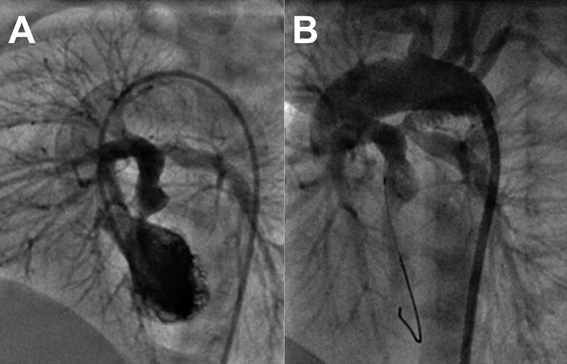

Surgery in DOLV in the presence of pulmonary stenosis depends on the age of the patient. Commonest repair option in patients with subaortic VSD beyond infancy is Rastelli surgery to route left ventricle to aorta and connect pulmonary artery to right ventricle through an extracardiac valved conduit.7) Pulmonary artery translocation after suture closing the stenosed pulmonary valve is another option if conduits are unavailable. Small infants may be palliated temporarily till definitive surgery. Provision of additional pulmonary blood flow may be achieved with an aortopulmonary shunt or percutaneous stenting of the ductus arteriosus. Improvement of intercirculatory mixing to prevent unfavourable streaming may be achieved by surgical atrial septectomy or percutaneous balloon atrial septostomy. One additional patient in our center with DOLV, subaortic VSD, d-malposed aorta was initially palliated in neonatal period with ductal stenting and balloon atrial septostomy (Fig. 6) followed later at one year with Rastelli surgery.

Journal of Pediatric Cardiology and Cardiac Surgery 5(1): 24-29 (2021)

Fig. 6 Ductal stenting in DOLV with severe pulmonary stenosis (Movie 5)

Left ventriculogram in left anterior oblique cranial view from an aortic catheter show a large aorta, small pulmonary valve, confluent pulmonary arteries, d-malposed aorta (A). After stenting of ductus arteriosus, aortogram fills the branch pulmonary arteries (B). The tip of the guidewire used for deploying the ductal stent is seen in the left ventricle confirming the origin of pulmonary artery from the left ventricle.